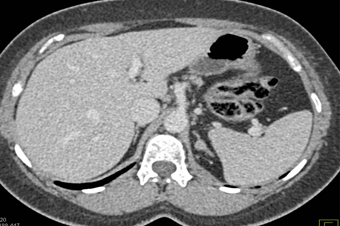

The most likely syndrome associated with the left adrenal nodule is?

Cushing’s Syndrome

Conn’s Syndrome

Turner’s Syndrome

McCune Albright Syndrome